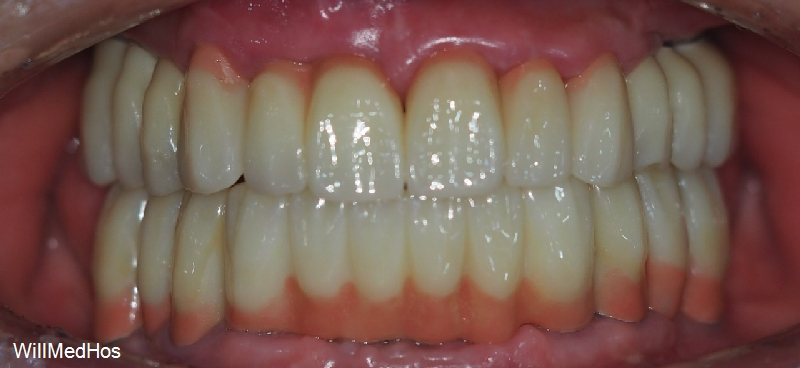

이렇게 치료가 다 마무리 되었고 최종 치료 소요 기간은 11개월 정도 되셨습니다.

현재 환자분은 치료에 대해 만족감이 매우 높으셨답니다.